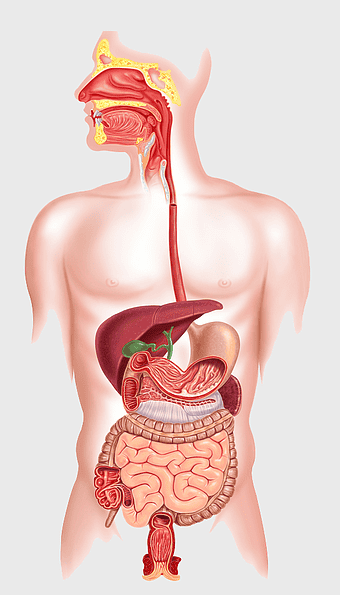

human gastrointestinal tract anatomy, human digestive system illustration, gastrointestinal disease symptoms, human body organ diagram, internal organ visualization, medical anatomy study, digestive health awareness -

human digestive system, gastrointestinal tract anatomy, liver function, stomach and intestines, digestive health, internal organs diagram, human body systems -

human digestive system illustration, gastrointestinal tract diagram, human body organ system, labeled digestive system, digestive anatomy chart, human internal organs, alimentary canal visualization -